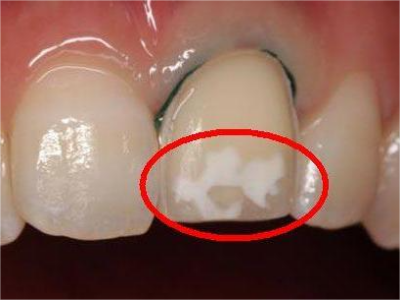

牙釉质发育不全牙表面上有坑图

牙釉质发育不全发展到严重时,导致牙釉质表面缺损,表现为带状、窝状的褐色凹坑,容易积存食物残渣诱发龋齿,表现为牙齿边上出现深褐色小洞。